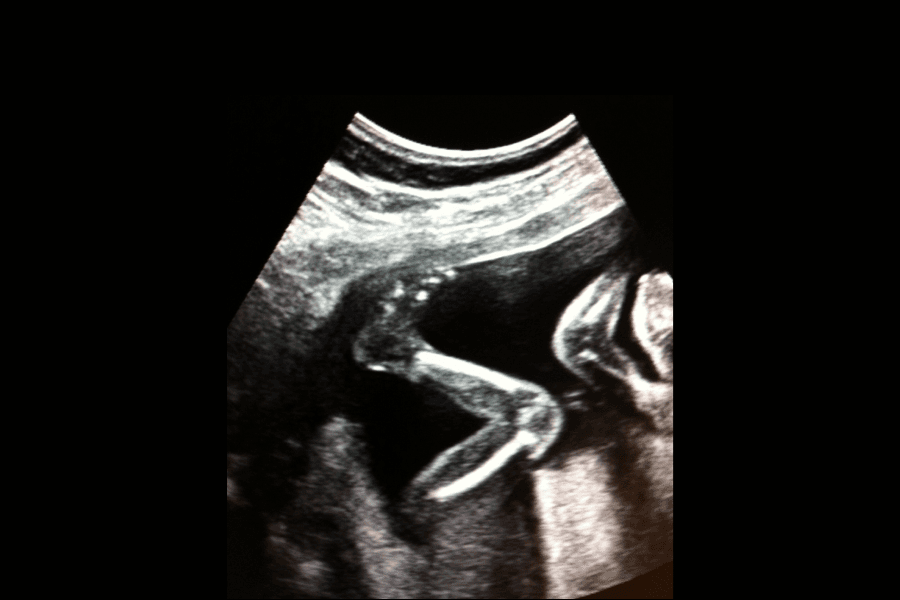

Lapsen liikkuminen kohdussa on yksilöllistä. Toiset liikkuvat paljon ja toiset vähemmän ja myös vuorokaudenaika voi vaihdella. Lapsen liikkeet voivat myös olla niin pieniä, että niitä voi olla hankalaa tai mahdotonta huomata. Lapsi potkii ja harjoittelee hengittämistä ja nielemistä, tarttumisheijastetta ja imemistä. Kaikki liikkeet eivät ole potkuja.

Siihen, miten odottava äiti tuntee sikiön liikkeet, vaikuttaa lapsen persoonallisuus, lapsen asento kohdussa ja istukan sijainti kohdussa.

On olemassa suuntaviivoja siitä, miten usein sinun tulisi tuntea lapsen liikkeitä raskauden aikana. Useimmat odottavat äidit tuntevat lapsen liikkeet ensimmäistä kertaa noin viikolla 20. Jos istukka on kohdun etuosassa, raskauden alkuvaiheessa on usein vaikeata huomata liikkeitä, mutta raskauden edetessä tunnet ne selvästi.

Kun olet alkanut tuntea lapsen liikkeitä, seuraava askel on kuulostella niitä joka päivä. Useimmat tuntevat liikkeitä päivittäin viikon 25 tienoilla. Kun lapsen liikkeet tuntuvat päivittäin, sinun tulee seurata niitä joka päivä. Voit myös alkaa tunnistamaan, milloin lapsi on hereillä. Kohdussa lapsella on usein hereilläolohetki iltaisin äidin rentoutuessa. Päiväsaikaan ollessasi itse liikkeellä lapsen liikkeiden tunteminen voi olla hankalampaa, ja joudut ehkä pysähtymään hetkeksi kuulostelemaan tunteaksesi niitä.